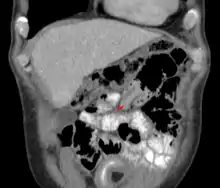

| An intussuception as seen on CT | |

The cause in children is typically unknown; in adults a lead point is sometimes present.[1] Risk factors in children include certain infections, diseases like cystic fibrosis, and intestinal polyps.[1] Risk factors in adults include endometriosis, bowel adhesions, and intestinal tumors.[1] Diagnosis is often supported by medical imaging.[1] In children, ultrasound is preferred while in adults a CT scan is preferred.[1]

An intussusception is often suspected based on history and physical exam, including observation of Dance's sign. A digital rectal examination is particularly helpful in children, as part of the intussusceptum may be felt by the finger. A definite diagnosis often requires confirmation by diagnostic imaging modalities. Ultrasound is the imaging modality of choice for diagnosis and exclusion of intussusception, due to its high accuracy and lack of radiation. The appearance of target sign (also called "doughnut sign" on a sonograph, usually around 3 cm in diameter, confirms the diagnosis. The image seen on transverse sonography or computed tomography is that of a doughnut shape, created by the hyperechoic central core of bowel and mesentery surrounded by the hypoechoic outer edematous bowel.[10] In longitudinal imaging, intussusception resembles a sandwich.[10] It is also called "pseudokidney" sign because hyperechoic tubular centre is covered by a hypoechoic rim producing a kidney-like appearance.[11]